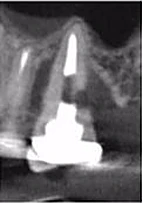

Bệnh nhân nữ 68 tuổi chuyển tới phòng khám của tôi sau khi bác sĩ tổng quát thấy tổn thương “nghi ngờ” nhưng không xác định được. Bệnh nhân không có triệu chứng và cũng không rõ vì sao mình được chuyển tới đây. Sau khi khám lâm sàng, tôi nghi ngờ có tổn thương ngoại tiêu. Tuy nhiên, bệnh nhân vẫn còn nghi ngờ về phim 2 chiều (Hình 8), thông tin trên phim chưa đáng để lo lắng, do đó cô ngần ngại chấp nhận điều trị.

Hình 8: XQ trước điều trị

Hình 10: Lát cắt ngang trên CBCT

Tuy nhiên, phim 3D cho thấy rõ ràng có tổn thương ngoại tiêu (Hình 9 và 10). Trên phim cũng đồng thời cho thấy tổn thương là ngoại tiêu cổ răng xâm nhập ở mặt trong. Trong buổi hẹn tư vấn, tôi đã cho bệnh nhân quan sát rõ tổn thương và đưa ra đề xuất điều trị.

Trường hợp này bắt đầu từ chẩn đoán không chắc chắn của bác sĩ tổng quát, sau đó là điều trị kết hợp nội nha và nha chu. Bệnh nhân được chuyển tới bác sĩ nha chu để lật vạt mặt trong và nạo bỏ tổn thương, hàn bằng Geristore® (Hình 11). Nhận thấy tổn thương vào tủy do đó bác sĩ nha chu chuyển về và điều trị tủy tại phòng khám của tôi (Hình 12).